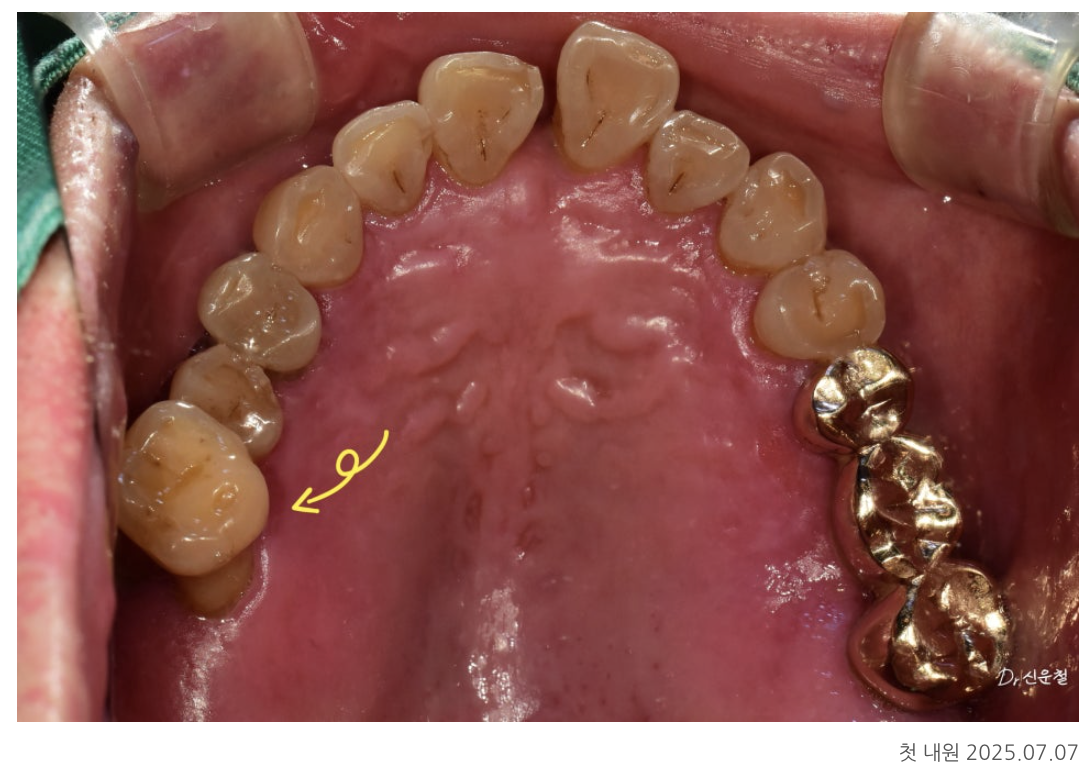

첫 촬영(파노라마·구강 사진)에서 크게 4가지 문제가 확인됐습니다.

① 아래 어금니 상실 → 위 치아 정출(내려옴)

오래전 빠진 아래 어금니 때문에

맞물리는 위 치아가 천천히 아래로 내려오는 정출이 진행되어 있었습니다.

② 앞니가 제자리에서 벗어난 ‘전위 치아’

위 앞니는

잇몸 약화

치아 사이 공간 증가

한쪽 방향으로 반복된 씹는 습관

때문에 앞쪽으로 밀려 나온 상태(전위)였습니다.

③ 치아 목 부분의 치경부 마모

잘못된 양치가 오래되면

치아 목이 깎여 시린 증상이 심해집니다.

해당 환자분도 송곳니·작은 어금니 부위에서

눈에 띄는 패임이 확인됐습니다.